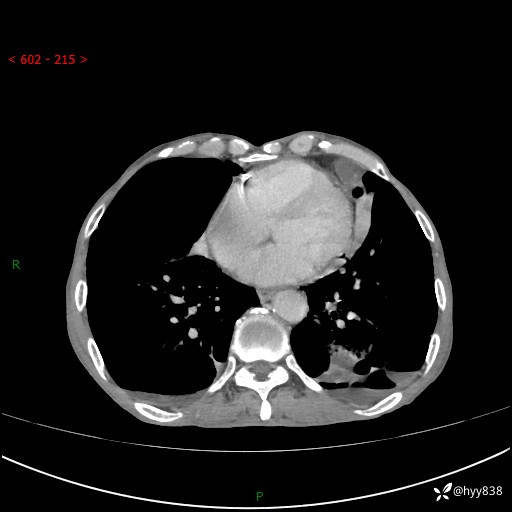

胸部CT平扫+增强